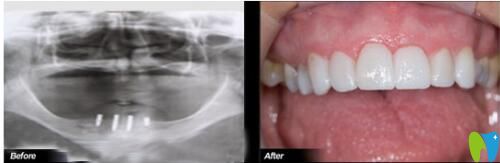

一位68歲朱老伯在沈陽(yáng)歡樂(lè)口腔做完“一日得”種植牙說(shuō)道:

“我先后換了5副活動(dòng)假牙,都抵不上4顆種植牙,14年前就開始掉牙,烤瓷牙沒(méi)法做,活動(dòng)假牙換了一回又一回,戴不牢;來(lái)到沈陽(yáng)歡樂(lè)口腔時(shí),是在原有的假牙上鉆孔、固定、生根,做完當(dāng)天晚上就吃上大螃蟹了!”

68歲叔叔在歡樂(lè)仁愛(ài)口腔做完種植牙前后對(duì)比照